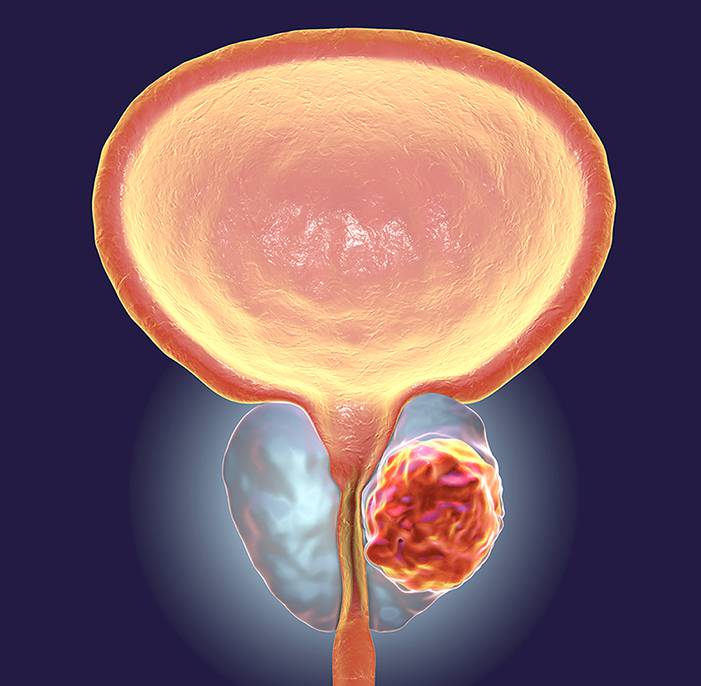

Η διουρηθρική εκτομή του προστάτη, η παλιά και γνωστή σε όλους μας Turis , που αποτελούσε τον ‘’χρυσό κανόνα’’ μέχρι σήμερα στην αντιμετώπιση της καλοήθους υπερπλασίας , και μας συνόδευσε επάξια για πάνω από μισό αιώνα μετά την εισαγωγή της από την Αμερική από πατέρες της Ελληνικής Ουρολογίας , φθάνει σιγά σιγά στα όρια των δυνατοτήτων της και παίρνει την θέση της στην Ιστορία της Επιστήμης.

Στην αυγή των νέων εξελίξεων της τεχνολογίας, νέες μέθοδοι ελάχιστα επεμβατικές , εύκολες και προσιτές στον ασθενή , μετά από λαμπρή πορεία στο εξωτερικό έρχονται να ενσωματωθούν στην φαρέτρα των σύγχρονων τεχνικών που πρέπει να διαθέτει ένα κέντρο αντιμετώπισης προστάτη στην Ελλάδα του σήμερα. Μία είδηση που έρχεται να ανακουφίσει χιλιάδες συμπολίτες μας , καθότι τα δύο τρίτα των ανδρών άνω των πενήντα βιώνουν σε διαφορετικό βαθμό τις επιπτώσεις της διόγκωσης του προστάτη τους , με λειτουργικά συμπτώματα που μειώνουν την αυτοπεποίθησή τους οδηγώντας τους σε κατάθλιψη και διαταραχή του ύπνου τους , της κοινωνικής τους ζωής και της σεξουαλικής τους λειτουργίας.

Οι τεχνικές είναι η REZUM και η HoLEP, αναίμακτες και ανώδυνες, που απελευθερώνουν τον ασθενή αυθημερόν διατηρώντας για πρώτη φορά τις ‘’ζωτικές’’ ανδρικές του λειτουργίες , γεγονός που η αδυναμία των παλαιών μεθόδων ως προς αυτό λειτουργούσε αποτρεπτικά μέχρι σήμερα στο να ζητήσουν βοήθεια από τον ειδικό.

REZUM: Η μέθοδος απευθύνεται σε άνδρες με μέγεθος αδένα έως 80cc που αφενός δεν θέλουν να απωλέσουν την στύση και την επσπερμάτισή τους και δεν θέλουν να ταλαιπωρηθούν επίσης με νοσηλείες, νάρκωση και απομάκρυνση από τις επαγγελματικές και κοινωνικές τους συνήθειες επί μακρόν. Γίνεται υπό την επήρεια απλής μέθης, διαρκεί δέκα λεπτά και ο ασθενής σε μία ώρα επιστρέφει στις δραστηριότητές του, όπως μας εξηγεί ο Xειρουργός Ουρολόγος Νικόλαος Μπαφαλούκας.

Χρησιμοποιεί την φιλική θερμική ενέργεια του υδρατμού με την μέθοδο της συναγωγής, θεμελιωδώς διαφορετικά δηλαδή από ότι γνωρίζαμε μέχρι σήμερα , επιφέροντας σε διάρκεια δύο τριών εβδομάδων συρρίκνωση μόνον του πάσχοντος τμήματος του προστάτη , δηλαδή της διάμεσης ζώνης και του μέσου λοβού.